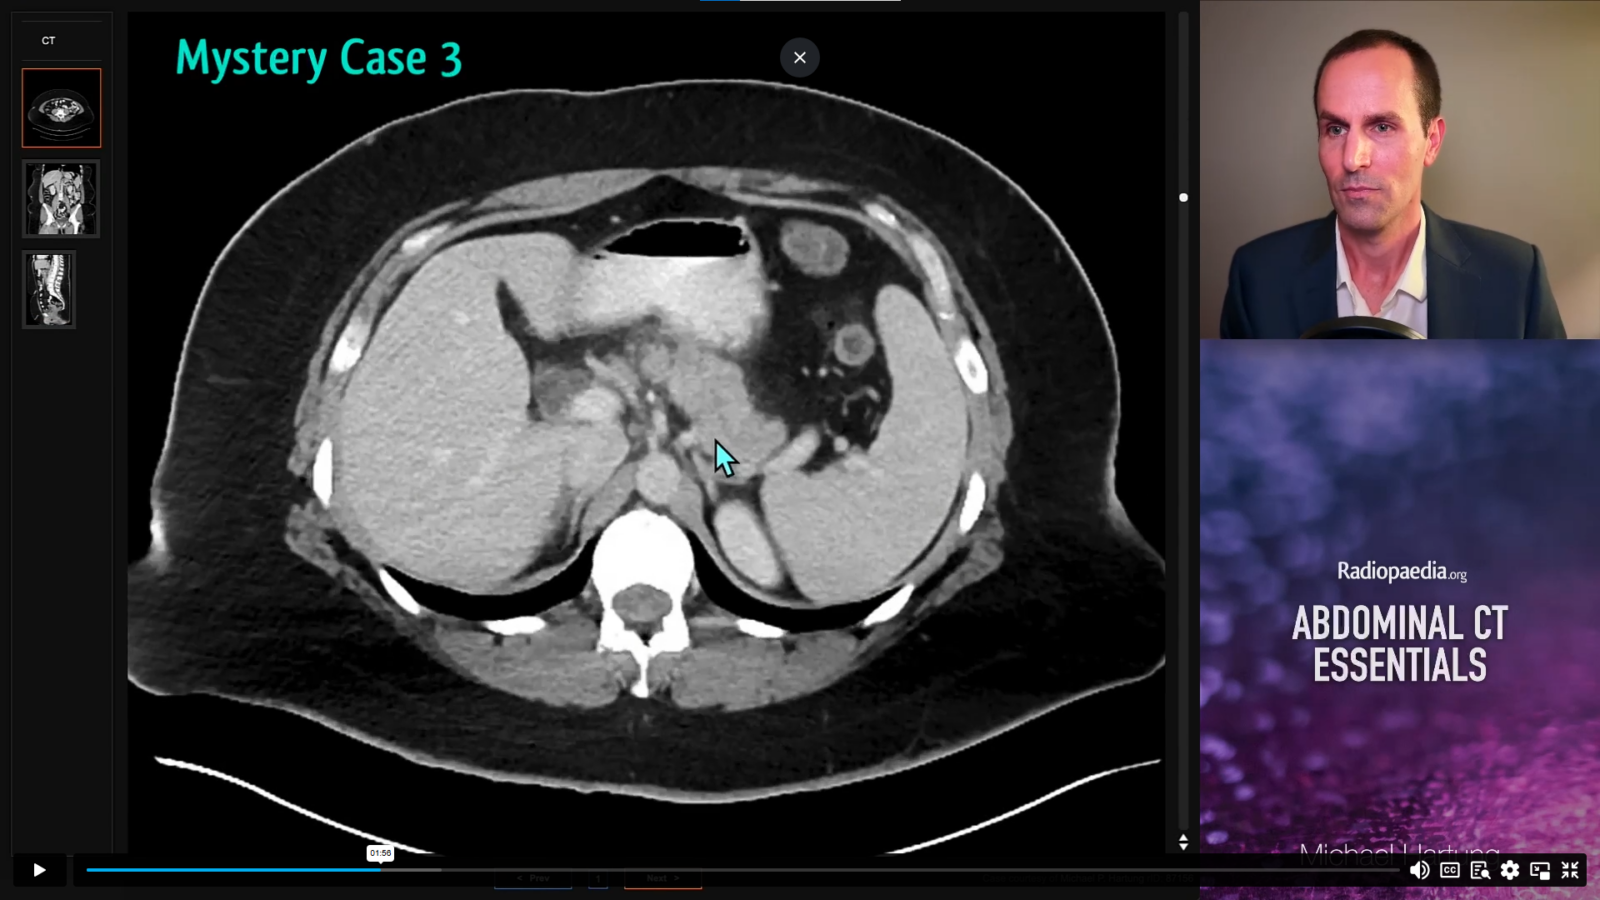

Michael Hartung, MD collaborated with Radiopaedia to launch a continuing medical education course, Abdominal CT Essentials, which covers abdominal CT protocols, search pattern, acute abdomen and cancer imaging. Through interactive cases and video lessons, Dr. Hartung addresses common diagnoses ranging from appendicitis and pancreatitis to liver tumors and cancer mimics.

The course features two and a half hours of video lessons and over 150 teaching cases for participants to hone and test their skills as they progress at their own pace. Dr. Hartung is no stranger to delivering radiology lectures and embraced the challenge of producing a video course as an exciting way to reach radiology trainees worldwide.